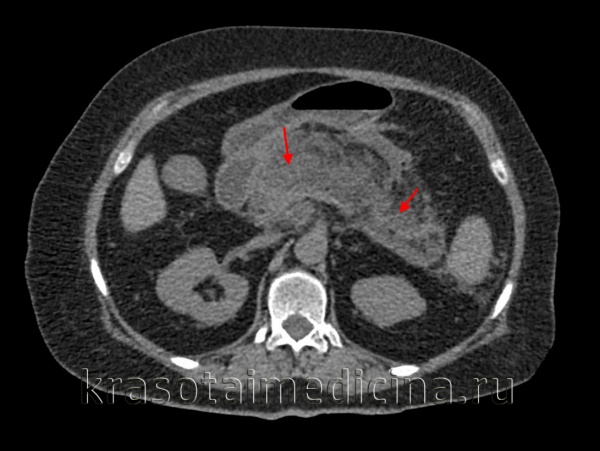

(Левый) На поперечном УЗ срезе определяется увеличенная гипоэхогенная поджелудочная железа, что характерно для острого панкреатита. Спереди от железы определяется скопление жидкости. Наличие и распространенность некроза оценить трудно.

(Правый) У того же пациента при КТ с контрастным усилением на поперечной томограмме большая часть поджелудочной железы не контрастируется, что указывает на развитие некроза; в хвосте железы определяется остаточная жизнеспособная ткань. Граница между передним краем поджелудочной железы и очагом острого некроза различима с трудом.

КТ ОБП. Панкреонекроз. Диффузный отек и нарушение структуры поджелудочной железы, отсутствие накопления контраста в ее паренхиме.